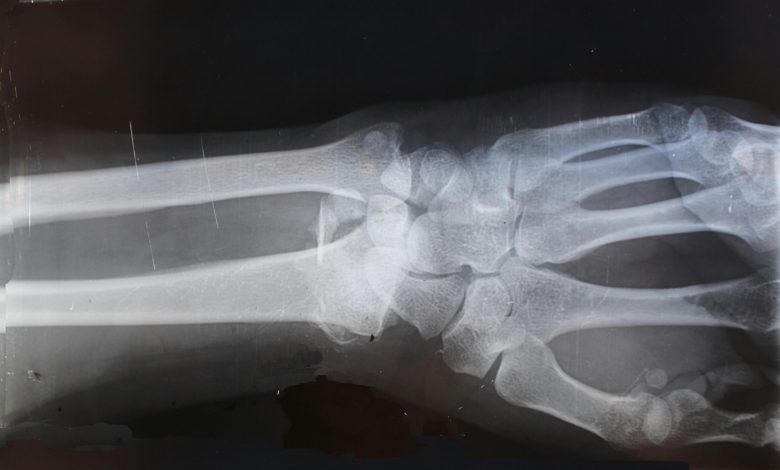

O osteossarcoma é o tipo mais comum de câncer ósseo e geralmente se desenvolve nos braços ou nas pernas. Os sintomas podem incluir dor óssea, caroço ou inchaço e osso que quebra facilmente. Os especialistas estimam que menos de 1.000 pessoas nos EUA desenvolvem osteossarcoma a cada ano. Cerca de 7 em cada 10 pessoas sobrevivem se a doença não se espalhar para outras partes do corpo, mas apenas 2 em cada 10 crianças sobrevivem se a doença se espalhar para fora do local ósseo original.